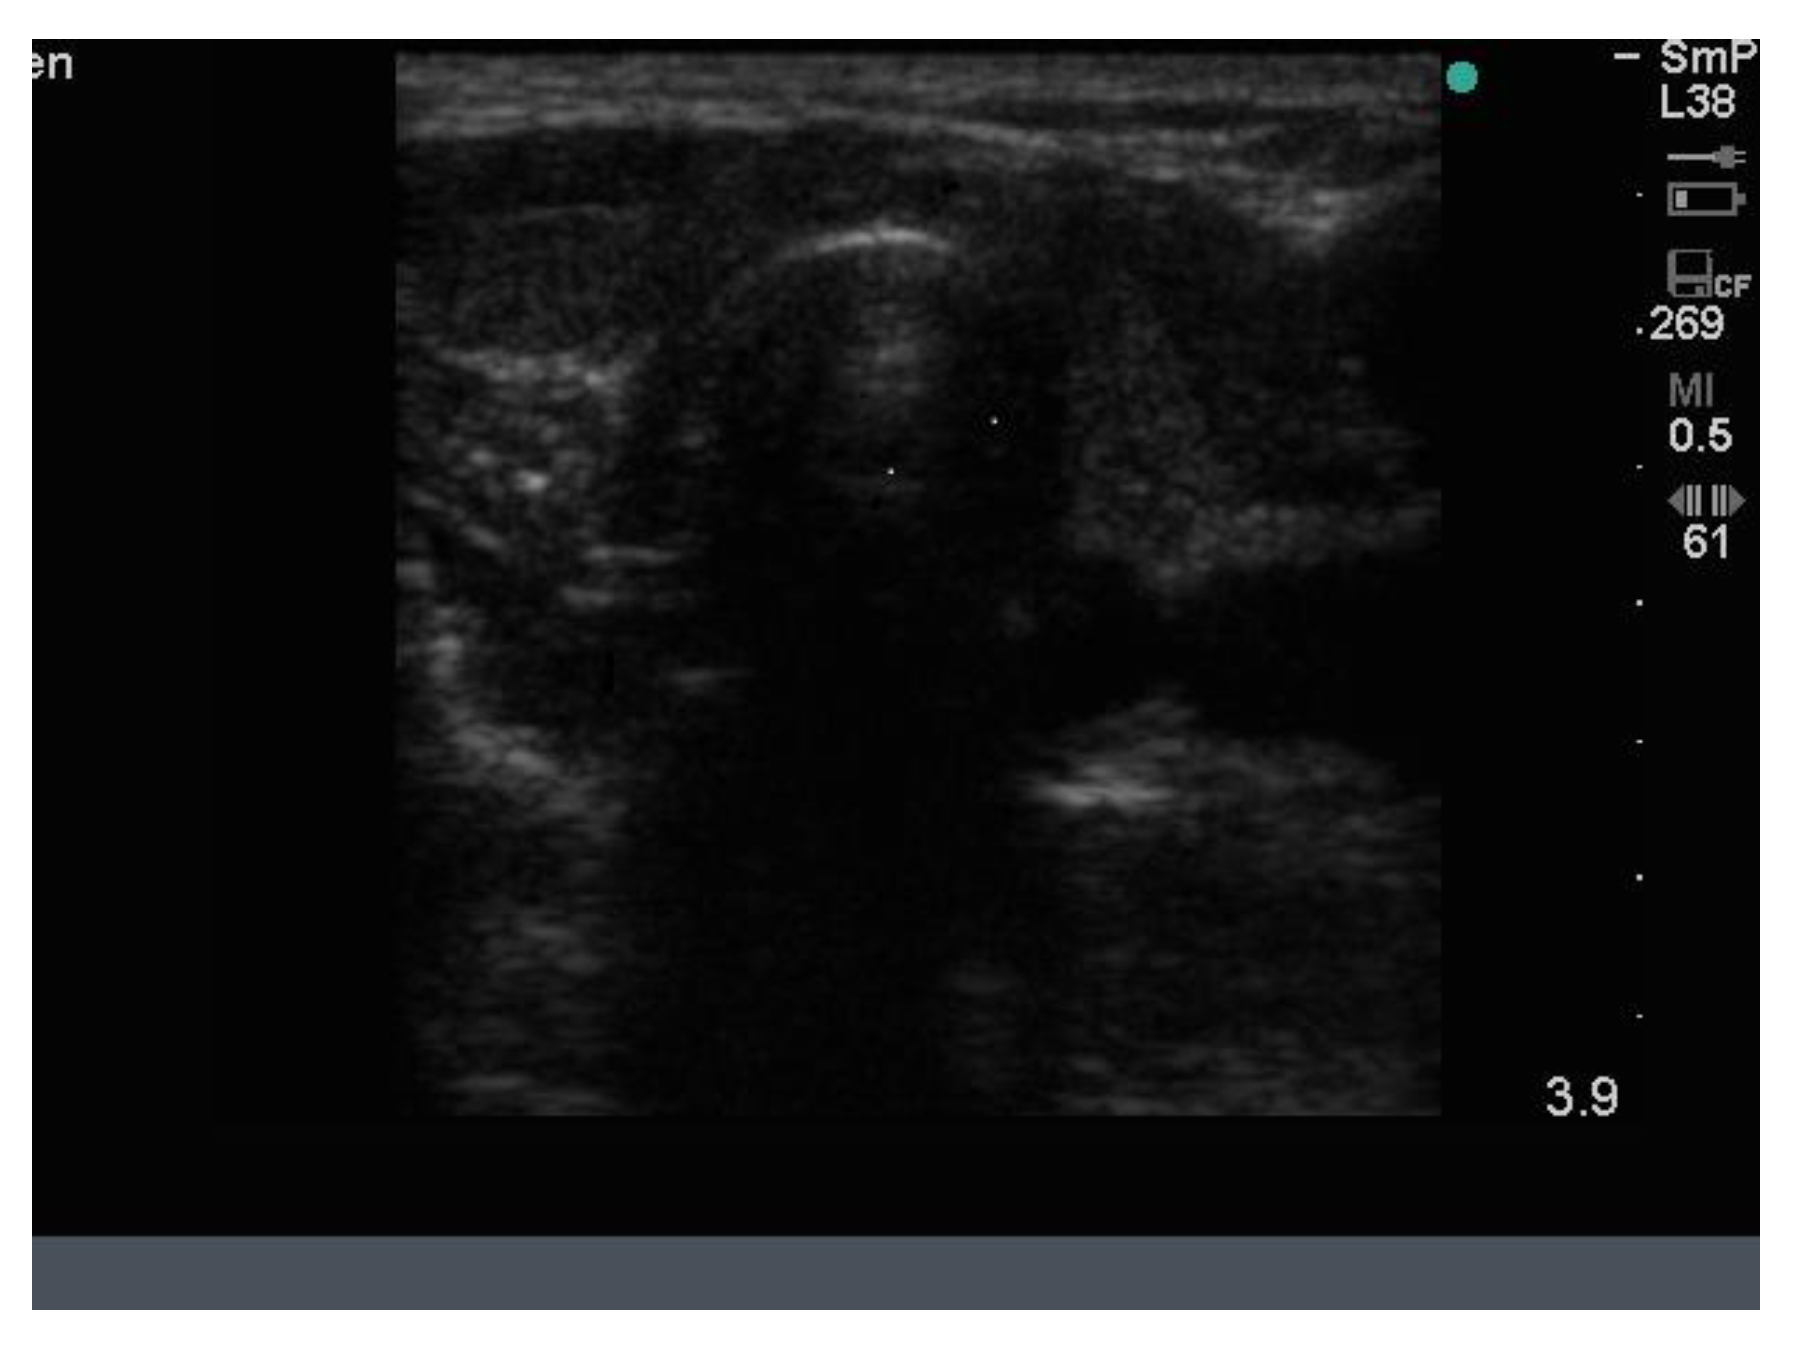

14. Parathyroid Disease

Because the senior author (JW) routinely measures serum calcium, parathyroid hormone (PTH) and vitamin D in his patients, hyperparathyroidism due to a benign adenoma of one of the parathyroid glands appears to be much more common than previously thought. The parathyroid glands are hidden behind the thyroid and so may be obscured by thyroid nodules, although they can often be seen in the longitudinal view below the lobes, as a hypoechoic lesion of around 1 cm in diameter (Figure 18).

The parathyroid adenoma is typically hypoechoic by comparison to the nearby thyroid tissue, which is consistent with the author’s experience. However, only about 50% of subsequently proven parathyroid adenomas are seen on ultrasound and even the Sestamibi nuclear scan fails to pick them up in about 30% of cases.

Figure 18. Thyroid ultrasound from a patient with hyperparathyroidism showing a hypoechoic lesion below the right thyroid lobe that was confirmed to be a parathyroid adenoma at surgery.